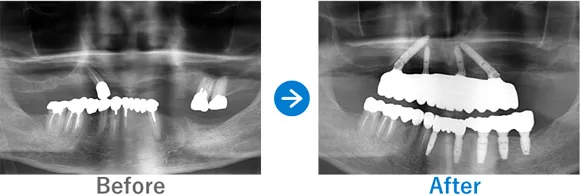

Case4

フルマウスインプラントで、食事も旅行も楽器も楽しめる人生の再スタート!

入れ歯を使用中。重度の歯周病で残っている歯もぐらぐらしている

上顎 オールオン4ダブルザイゴマ、下顎 オールオン4

10,318,000円(上顎6,743,000円、下顎3,750,000円/内訳:上顎オールオン4(ノーベルザイゴマインプラント4本)、下顎オールオン4(ストローマンインプラント4本)、3Dモデルガイド*、仮歯、セデーション、ボツリヌストキシン注射、3D模型、保証10年)

来院の背景

入れ歯を作ったものの、重度の歯周病で前歯もぐらぐらしており噛むことが難しく、入れ歯をかけている歯もダメージを受けている状態でした。入れ歯をやめて、友人と気兼ねなく食事をしたり、旅行を楽しんだり、楽器を吹いたりすることをご希望です。

治療結果

ご家族のうち、歯が悪いのは患者さまのみでコンプレックスがあったそうです。今回、思い切って治療を受けてよかった! とおっしゃっていました。30代から糖尿病の治療薬を服用されています。糖尿病は歯周病のリスクが高いので、今後もインプラント周囲炎のリスク管理が重要です。